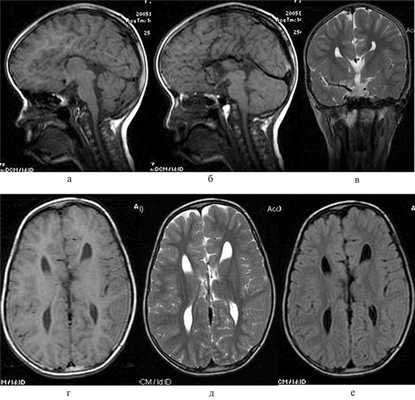

Рис. 3. МРТ-картина аплазии мозолистого тела у девочки Р., 12 лет, с РН. На сагиттальных FSE Т1ВИ (а, б) мозолистое тело не дифференцируется, обращает внимание расширенное отверстие Можанди (а) при относительно сохранном объеме мозжечка; миндалины его незначительно опущены (б) — до входа в большое затылочное отверстие. При этом отмечается незначительное расширение межполушарной щели и типичная «бабочка» боковых желудочков на FSE Т2ВИ в коронарной проекции (в). На аксиальных FSE Т1ВИ (г) и ТЕ2ВИ (д), FLAIR Т2ВИ (е) вместо мозолистого тела видна несколько расширенная межполушарная щель с характерным для аплазии мозолистого тела изменением конфигурации желудочков.